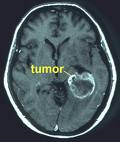

9 de febrero de 2017 · 1122 lecturasCambios sospechosos en la evolución de los tumores cerebrales en Reino Unido: el Glioblastoma multiforme (GBM) se incrementa y otro tipo de gliomas malignos menos agresivos disminuyen.

Revista MicroWave News, 31 de enero de 2017. La incidencia de glioblastoma multiforme (GBM), el tipo de cáncer cerebral más virulento y letal, está aumentando en Reino Unido, mientras que la incidencia de otros tipos de tumores cerebrales malignos está disminuyendo, según algunos datos publicados (…) -

Los tumores cerebrales aumentan en Dinamarca por el uso de los teléfonos móviles

24 de enero de 2017 · 10986 lecturasLos tumores cerebrales aumentan en Dinamarca por el uso de los teléfonos móviles

Según expone en enero de 2017 la Fundación para la protección contra la radiación de Suecia, los tumores cerebrales están aumentando en Dinamarca. Conforme a las últimas estadíticas existentes, el número de personas diagnosticadas con tumores del sistema nervioso central (incluidos los tumores cerebrales) en Dinamarca se ha incrementado más del doble desde 1990, correspondiendo el mayor incremento a los diez (…) -

Nuevos estudios confirman el riesgo de glioma (un tipo de cáncer cerebral) asociado al uso de los teléfonos móviles

3 de diciembre de 2016 · 1730 lecturasNuevos estudios confirman el riesgo de glioma (un tipo de cáncer cerebral) asociado al uso de los teléfonos móviles

Lennart Hardell, oncólogo sueco de reconocido prestigio, que además es profesor en el "í–rebro University Hospital" en la ciudad de í–rebro, Suecia, acaba de publicar en su blog una noticia relativa a que unos nuevos resultados del proyecto Interphone, publicado en noviembre en la revista "American Journal of Epidemiology" , confirman el riesgo del glioma asociado al uso de (…) -